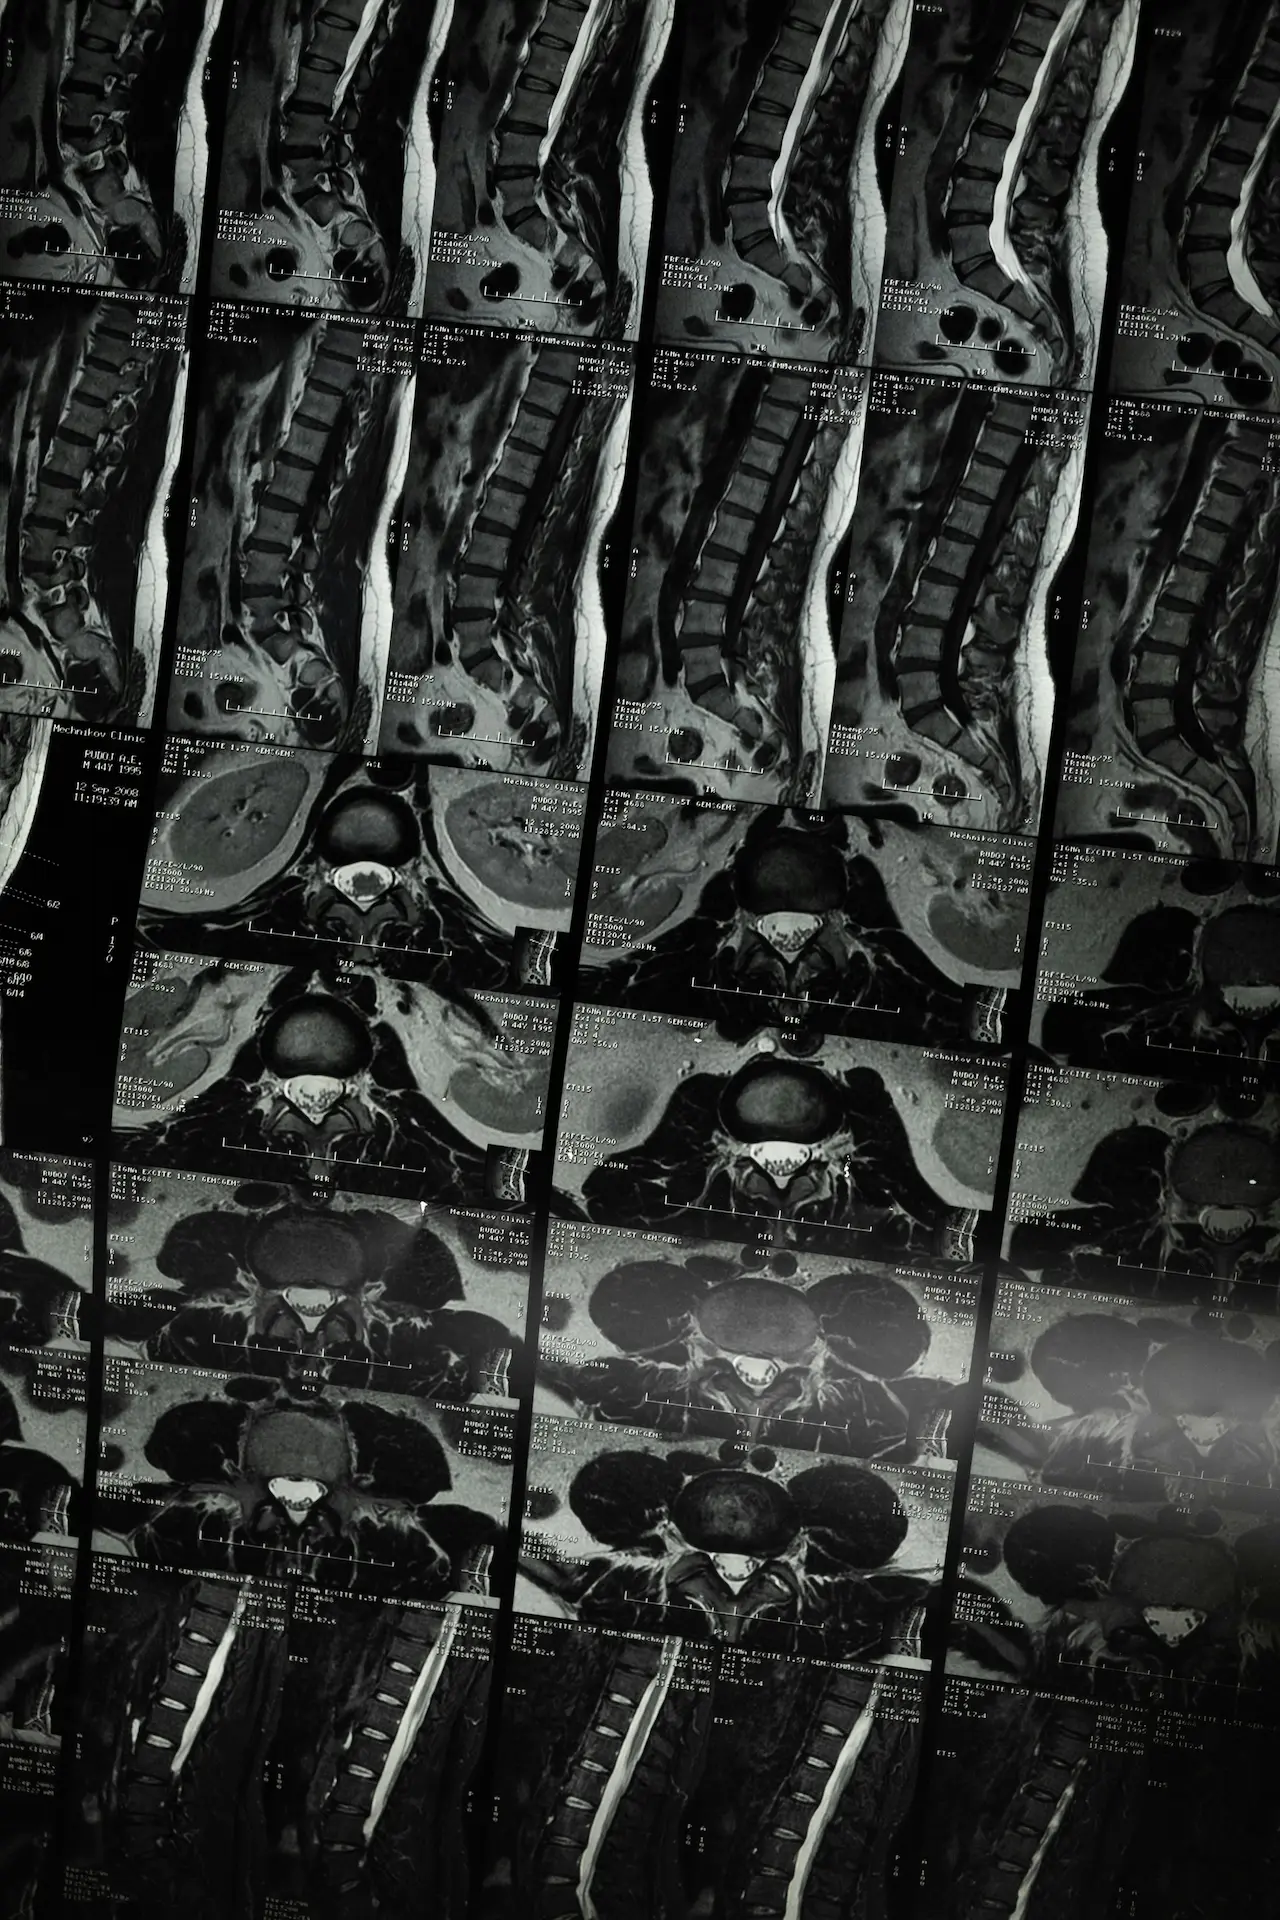

If imaging is relevant, your practitioner may discuss this with you and/or recommend liaising with your GP. Many episodes of back pain can be managed effectively without scans, but imaging can be helpful in specific scenarios.

Not always. Many people with back pain improve without imaging. Scans may be recommended if there are red flags, significant nerve symptoms, trauma, or if symptoms aren’t improving as expected. Your practitioner can discuss whether imaging is likely to be helpful in your situation.